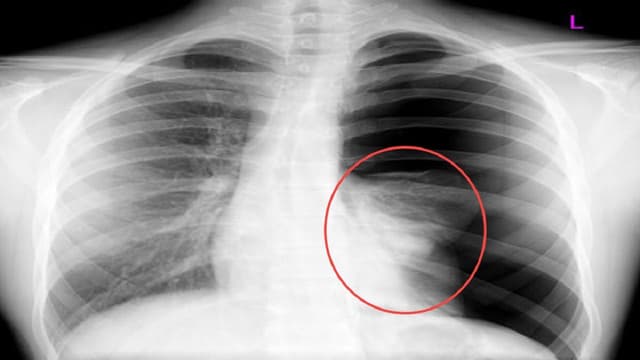

Viêm phế quản bệnh viêm nhiễm đường hô hấp dưới phổ biến, tác động lên phế quản và các nhánh. Khi bị viêm phế quản cấp j20, niêm mạc của các ống dẫn khí bị sưng phù, làm hẹp đường dẫn khí, làm xuất hiện các triệu chứng như ho, khạc ra đàm và khó […]